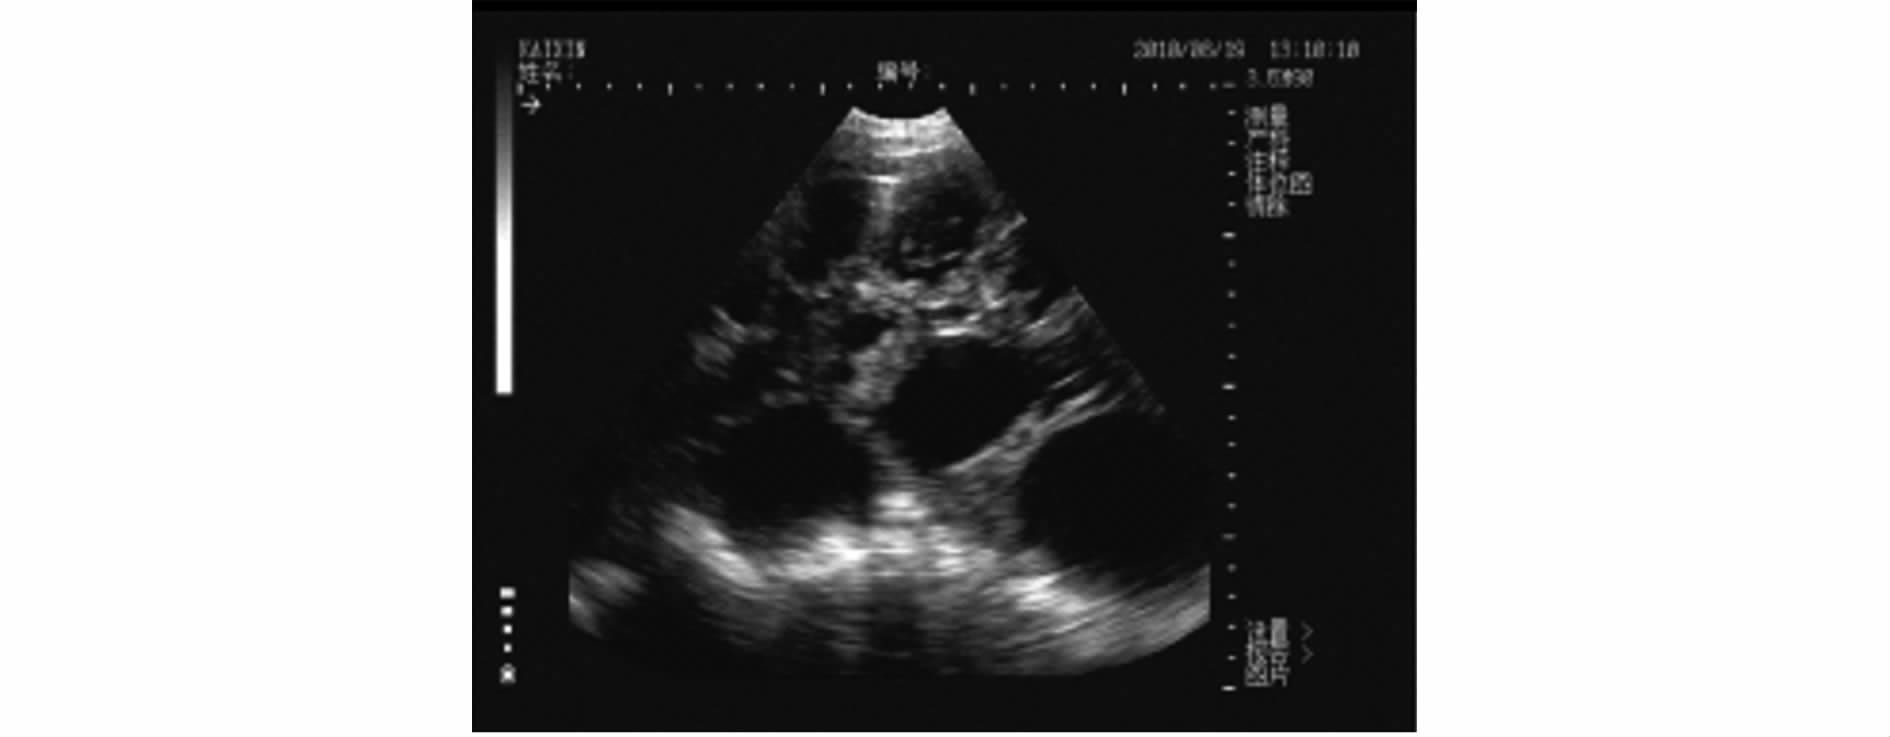

3.2.2 妊娠母猪 母猪妊娠的声像特征:妊娠初期子宫中出现孕囊,又称妊娠囊,内含初期胎水,量很少,对超声不产生反射,呈小的圆形暗区。在配种后19d、20d最早被扫查到时,暗区的直径在1.0cm左右,通常为一个暗区,有时可见2个或3个相邻的暗区(见图9),位于膀胱暗区的前下方或下方。为了便于B超操作者对B超成像进行有效准确地判断,作者专门附了一张母猪妊娠剖面与B超影像对比图(见图10)。

图10 B超影像与实体剖面图像对比